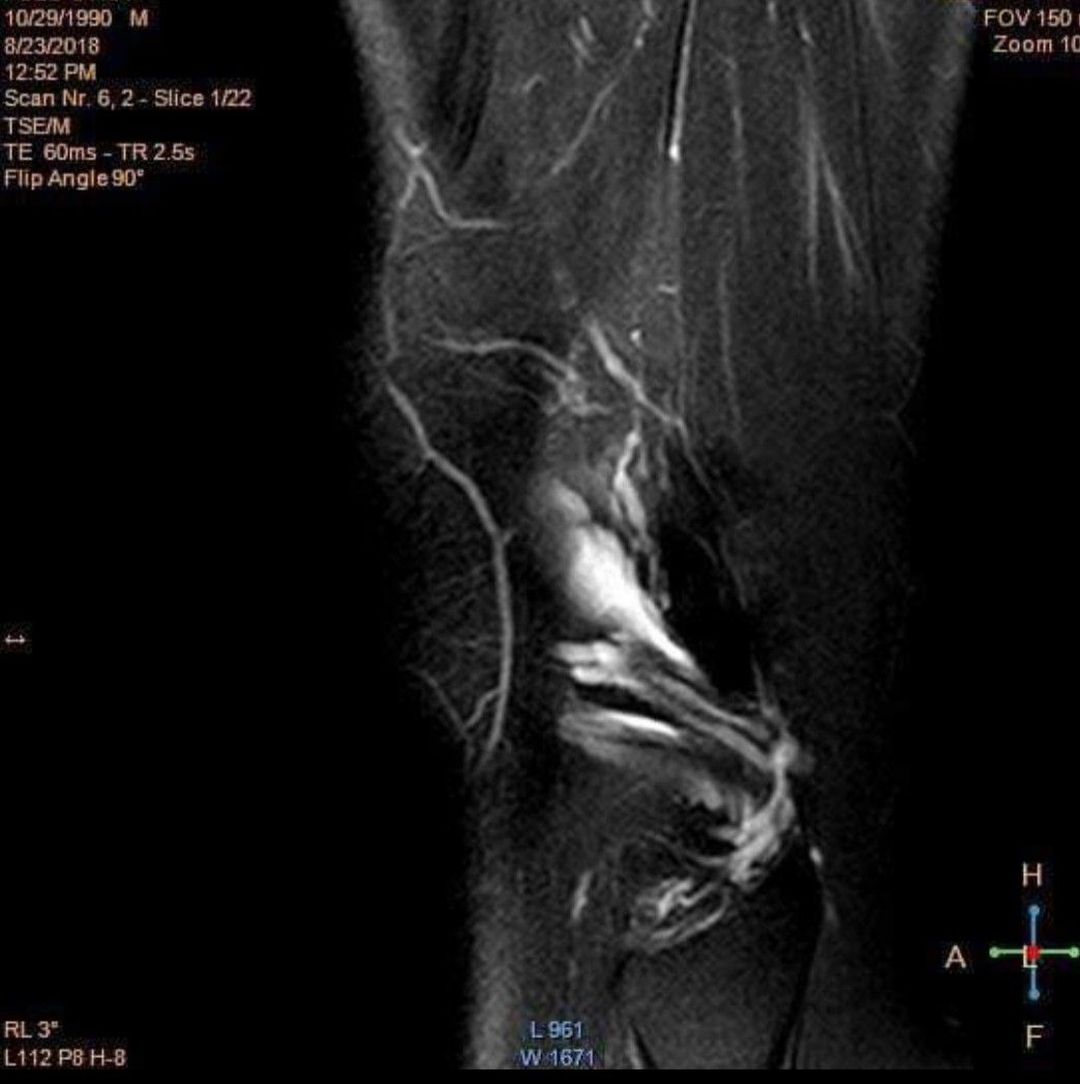

Diagnostic?

Patient having suffered several knee injuries playing football but decided not to do surgery.